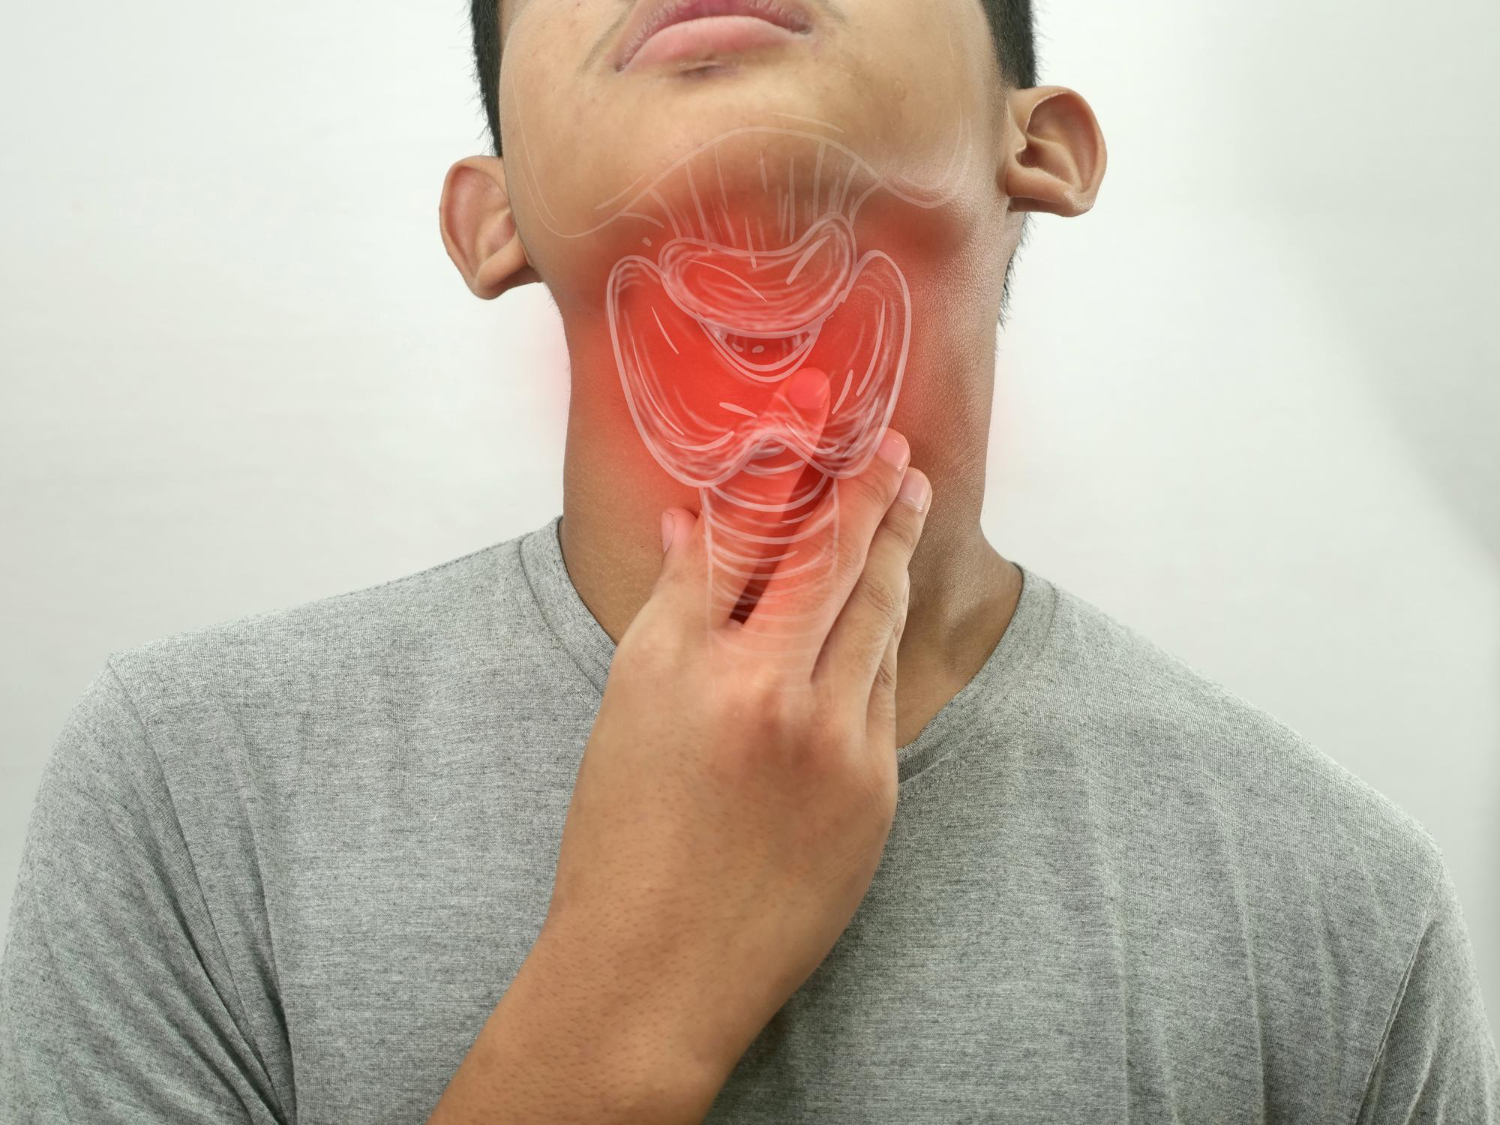

Suffering from swollen, painful tonsils? Our Denver ENT urgent care provides same-day diagnosis and treatment for tonsillitis and tonsil infections. No appointment necessary.

Sudden onset bacterial or viral infection causing severe throat pain and swelling.

Persistent or recurring tonsil infections occurring multiple times per year.

Serious complication where pus collects behind the tonsil, requiring urgent drainage.

Viral infection causing extremely swollen tonsils, fatigue, and prolonged symptoms.

Our ENT specialists perform detailed examination of your tonsils, throat, and lymph nodes.